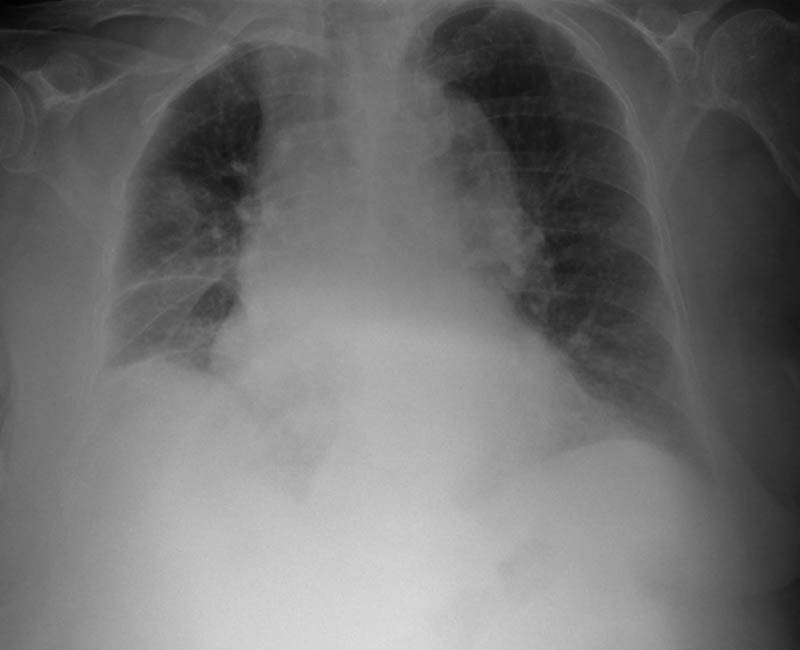

Fibrosis pulmonar. ICC.